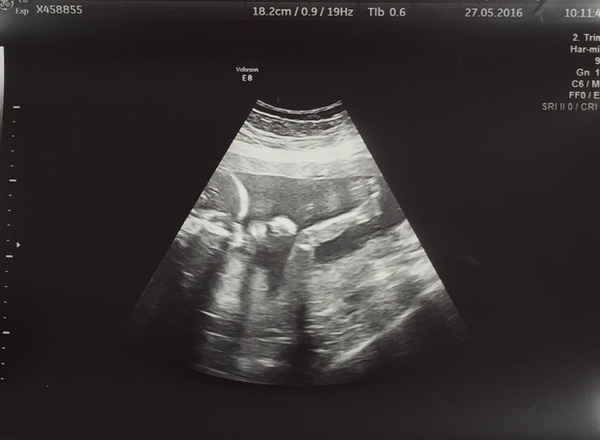

Yes me Northern, I've got anterior placenta had my 20 week scan on Thursday - we're having a boy! And he did not stop moving, but I couldn't feel a thing! There were arms and legs going everywhere and he was twisting and turning the whole time but I couldn't feel it!

I've felt a few things over the weekend but because it's so quick and faint it's hard to catch it, I can't wait until I feel proper kicks! I'm 21 weeks tomorrow

Glad it's not just me - 20 week scan showed loads of movement but nothing yet!

We had our 20 week scan today, which all went well! Lots of wriggling, which my DH has finally seen too, which is so lovely. Now we'll start to seriously look at buying things!

Glad to see scans all going well. I had mine yesterday too and was lovely to see baby wriggling around. I had to roll around quite a bit in order for them to get all the measurements they needed as baby kept chasing away. We didn't want to know the gender and before the scan I was worried I might see something to give it away but there was no telling as baby was wriggling so much and had either legs crossed or in the air!